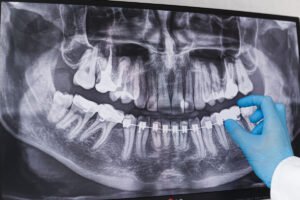

También tenemos que destacar la existencia de otros tipos de prótesis dentales, denominados implantes dentales. Estos se van a adherir a piezas de metal que se colocan debajo de las encías, directamente incrustados en los huesos del maxilar. La principal ventaja de los mismos es que permiten realizar mordidas más fuertes, sin el gravísimo problema que se produce con las dentaduras postizas y, que no es otro que el deslizamiento de la pieza. Estos deben ser colocados por dentistas profesionales que cuenten con la titulación exigida al efecto.